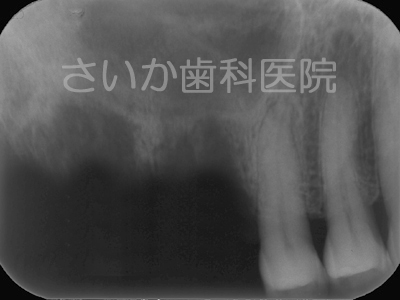

上の奥歯2本を歯周病で失ったため,骨が吸収しています。ヒトの上あご内部には「上顎洞」と呼ばれる空洞があるため,骨の厚みは矢印で示した厚みしかありません(上図右)。

「ソケットリフト」という治療法は「上顎洞」の底面部にインプラントを粘膜を破らないように突きだしてやる方法です。

手術後,しばらくしますと突きだしたインプラント周囲には骨が自然に出来てきます。骨の再生に人工的な物を使用せず,移植も必要としないため,患者様への負担は少ない治療法のひとつです。下の写真はインプラントを入れて5年が経過した写真です(パノラマレントゲンのため,画質が粗くなっています)。